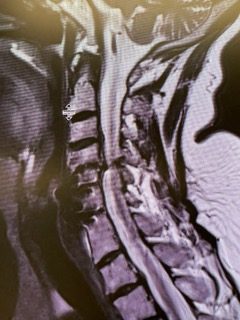

MRI was performed and did not reveal a stroke or hemorrhage but suggested a paucity of vasculature in the right intracranial circulation and a diagnosis of Moya-Moya, prompting a referral to NSPC’s neurovascular surgeon Dr. Jonathan Brisman.

Noninvasive vascular imaging was sufficiently suggestive to warrant conventional digital subtraction angiography, performed by Dr. Brisman and confirming Moya-Moya syndrome (Figures 1). CT Perfusion (Figure 2) showed a decreased transit time of blood to the right hemisphere and the patient was recommended to undergo cerebral revascularization to avert stroke.